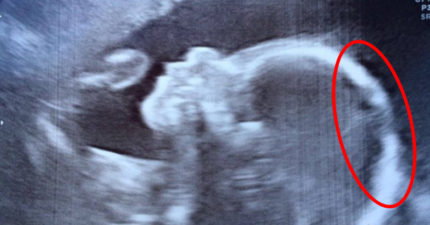

女娃超音波被拍到「過分濃密頭髮」,一出生「滿炸到醫生嚇呆」!(影片)